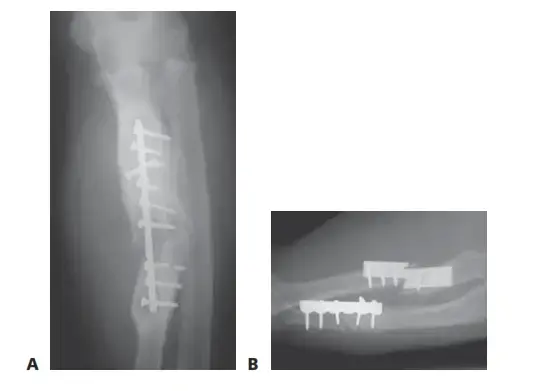

جراحة استبدال مفصل الركبة (Knee Arthroplasty):

- استبدال مفصل الركبة الكلي (Total Knee Arthroplasty - TKA): إجراء يتم فيه استبدال الأسطح المتضررة من عظم الفخذ والقصبة، وفي بعض الأحيان الرضفة، بمكونات صناعية مصنوعة من المعدن والبلاستيك الخاص. تُعد حلاً فعالًا جدًا لحالات خشونة الركبة الشديدة التي لا تستجيب للعلاجات الأخرى.

- استبدال مفصل الركبة الجزئي (Partial Knee Arthroplasty - PKA or Unicompartmental Knee Arthroplasty): يتم استبدال جزء واحد فقط من المفصل (عادةً الجزء الداخلي) بمكونات صناعية، عندما تكون خشونة الركبة محصورة في منطقة واحدة فقط.

تثبيت المكونات الاصطناعية:

* يتم تثبيت مكون معدني على نهاية عظم الفخذ.

* يتم تثبيت مكون معدني مسطح على الجزء العلوي من عظم القصبة.

* يتم إدخال قطعة بلاستيكية طبية عالية الجودة بين المكونين المعدنيين لتكون بمثابة غضروف مفصلي صناعي.

* في بعض الحالات، يتم استبدال السطح الخلفي للرضفة بمكون بلاستيكي.